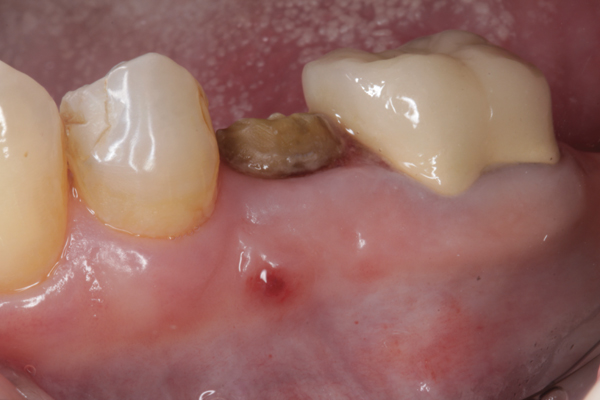

Fig 20. (Case 4) Radiograph of tooth No. 30, which had a hopeless prognosis.

Figure 20

Fig 21. Radiograph of extraction socket. Buccal plate was two-thirds resorbed.

Figure 21

Fig 22. Bone graft was placed in the socket and a d-PTFE barrier was used to cover the graft. The bone graft material was placed beyond the alveolar housing to accommodate shrinkage of graft material and to facilitate attaining a wide alveolar ridge. The barrier was removed after 5 weeks.

Figure 22